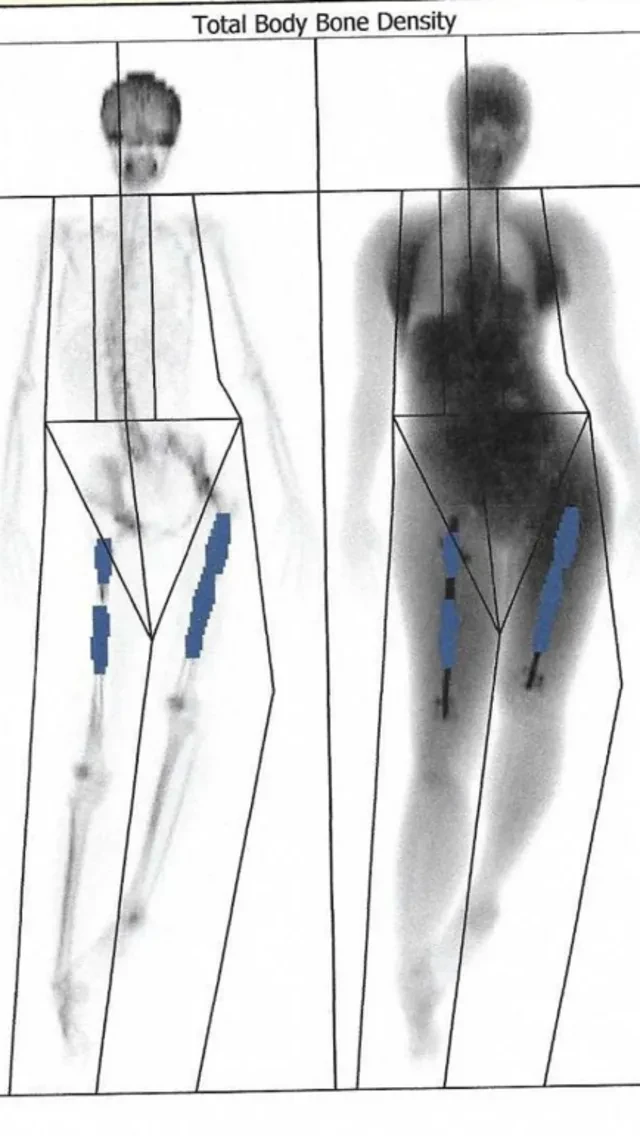

Elaine go do scan wey show say di nail for her left leg bin break through her femur, wey be di thigh bone, wey be di strongest bone for human being bodi.

Six weeks later, scans show say for her right leg, di bone don dey grow. Her femur just be two half of bone wey metal rod hold togeda.